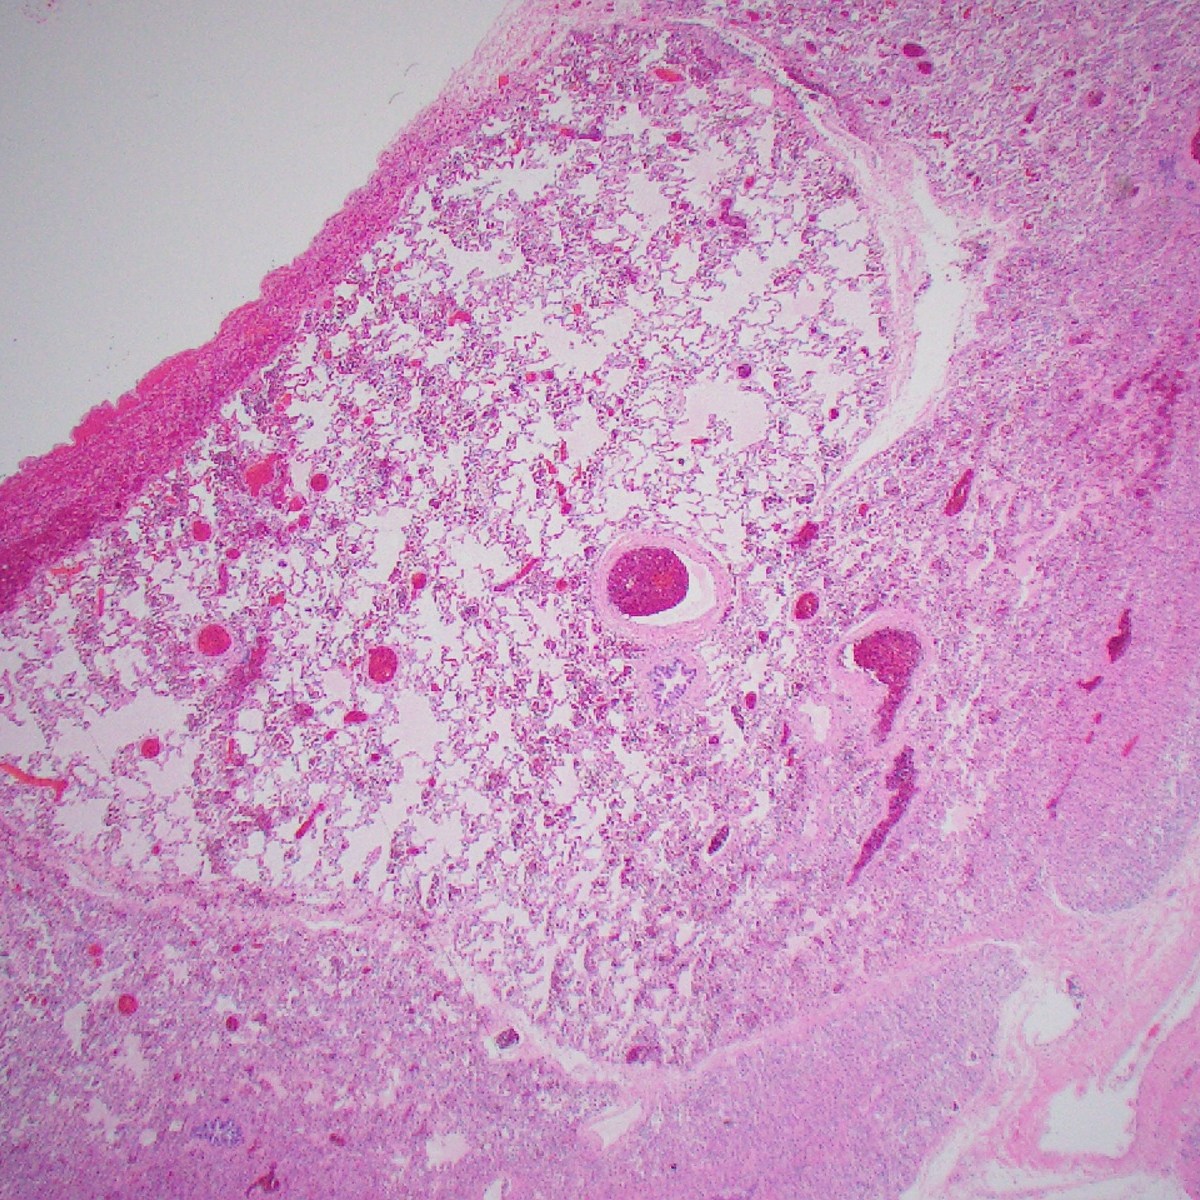

Case 3: Two years-old, large neck mass

Images

Hypercellular, monotonous spindle cell tumor, scattered mitoses; this case had TPM3::NTRK1 fusion

IHC: CD34, S100, and panTRK are diffusely positive; this case had TPR::NTRK1 fusion

Diagnosis

NTRK1-associated Sarcoma